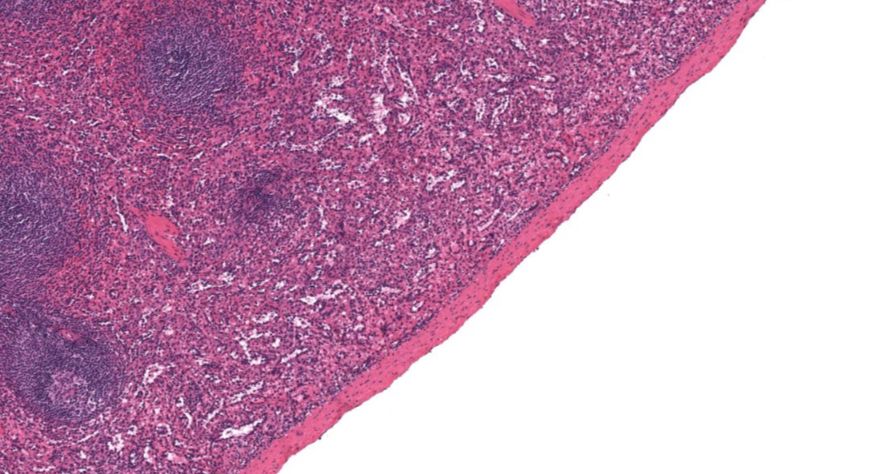

低倍镜:胸腺表面包有薄层结缔组织构成的被膜,结缔组织深入实质,将胸腺分成许多不完整的小叶。每个小叶分为周围的皮质和中央的髓质两部分。皮质中胸腺细胞排列密集,故染色深;髓质中胸腺细胞较少,胸腺上皮细胞多,故染色浅,其中可见染成红色的圆形小体-胸腺小体。高倍镜:胸腺小体大小不等,由几层至十几层扁平的胸腺上皮细胞呈同心圆状排列而成,其外周的细胞较幼稚,细胞核明显;小体中央部分的上皮细胞已退化,细胞核消失,胞质呈均质状,染成红色。

1.成人胸腺全景图

2.被膜

3.皮质

4.髓质